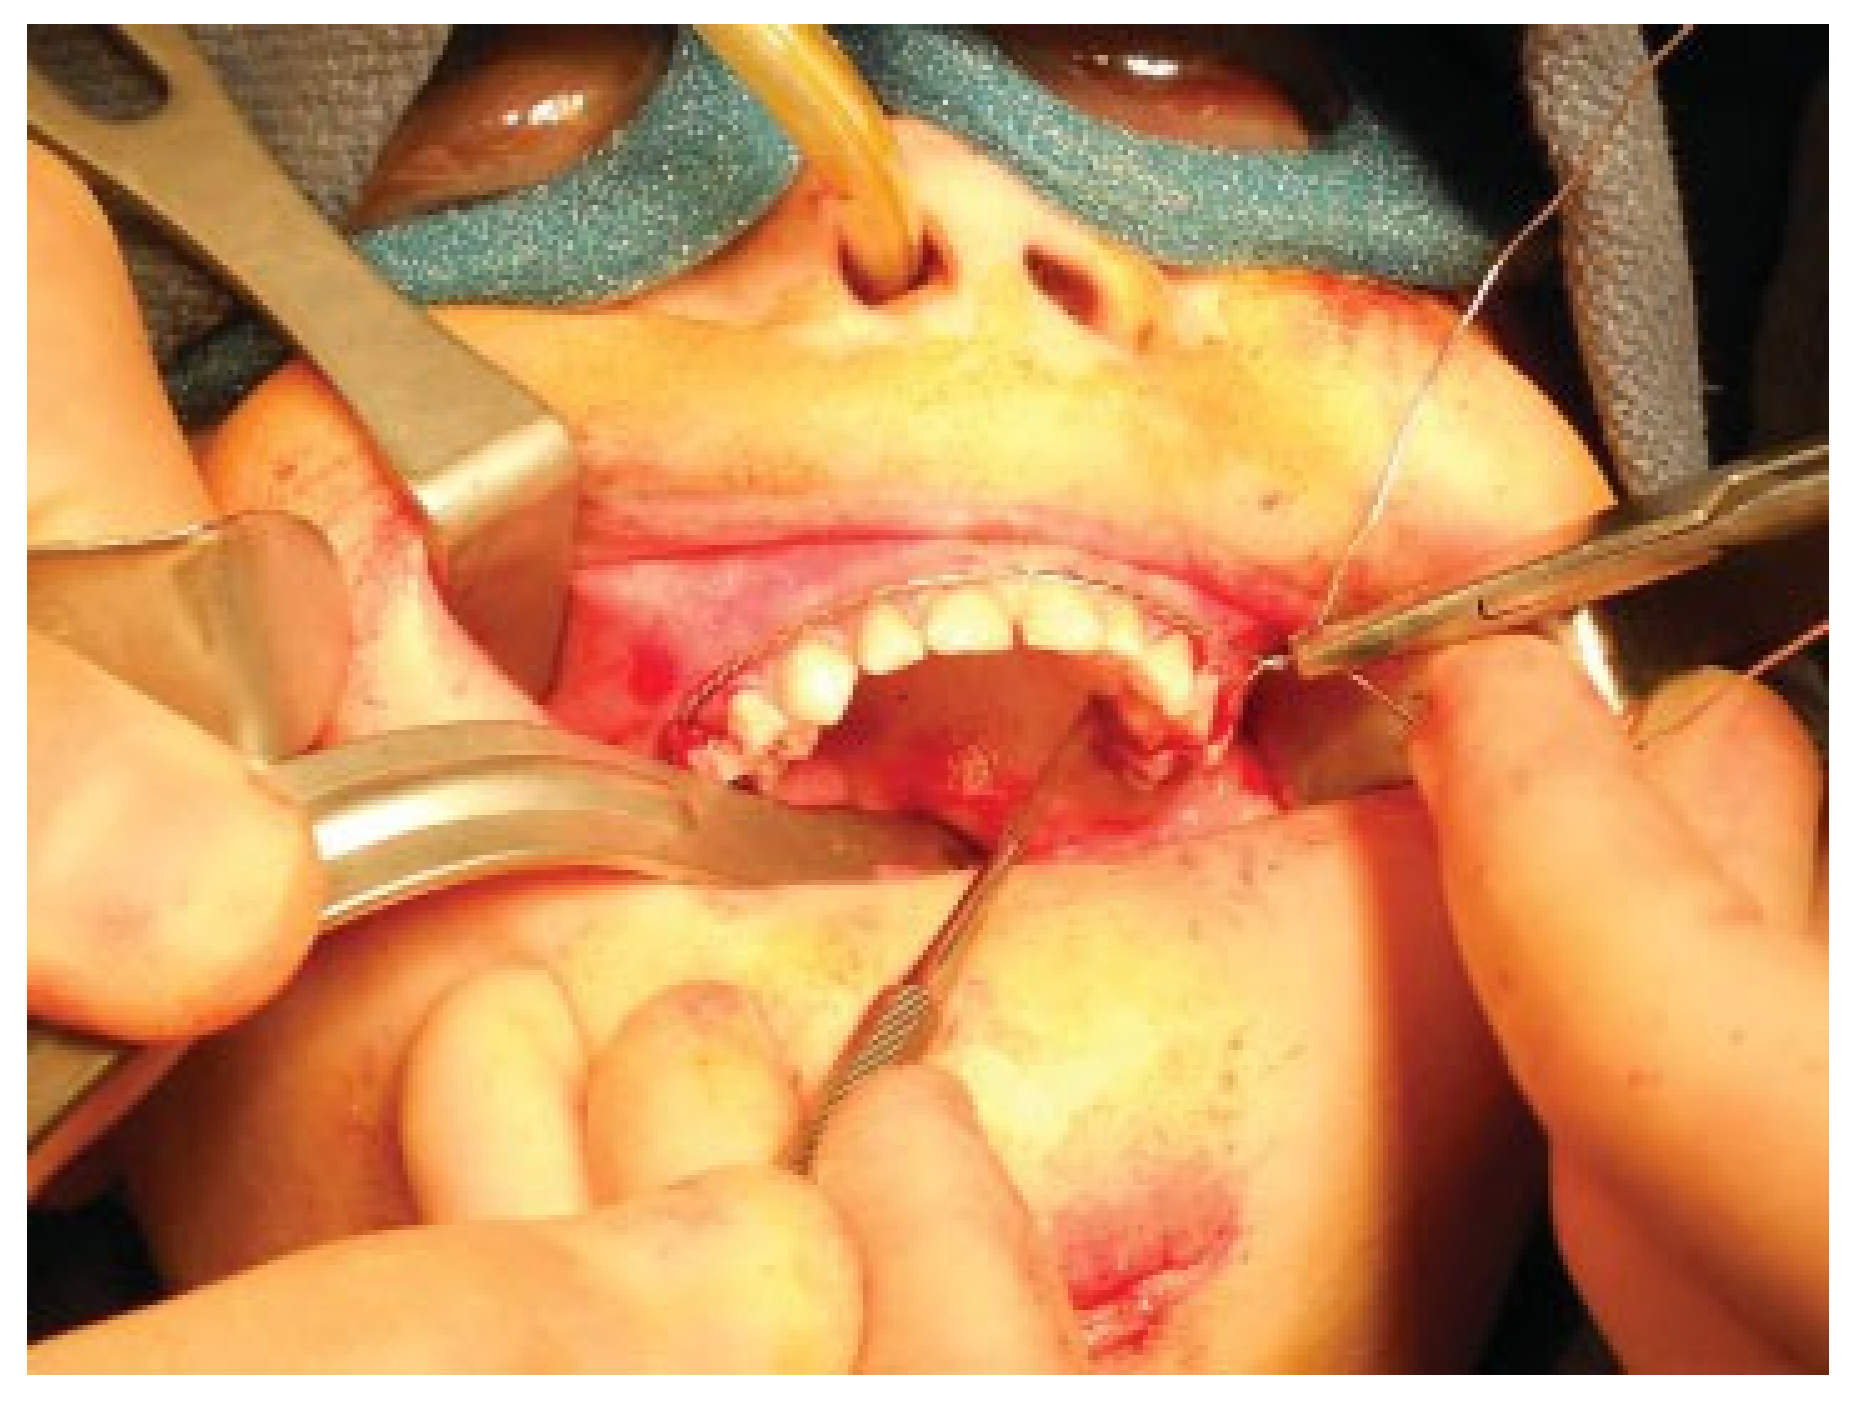

Modifications to this procedure include using 24-gauge stainless steel wire that is passed from the last molar as originally described (Figure 2). The wire is then twisted from one side of the dental arch to the other (Figure 3). Ideally, circumdental ligatures are passed to secure the individual teeth as the cable is being twisted (Figure 4). This will allow for secure fastening of the cable and ligature complex. Finally, when the wires composing the Risdon cable have reached the contralateral molar tooth, it is then secured and the final circumdental ligature is placed. The circumdental wires are cut and twisted in a traditional fashion that will allow loops for securing elastics or wiring to establish MMF or guiding functions (Figure 5). If elastics are used for MMF, it is most unusual for the Risdon wiring to pull off or otherwise fail as the elastics “give.” Aside from establishing MMF, this procedure may also be used for splinting avulsed or luxated teeth, and may be supplemented with autopolymerizing resin for stability (Figure 6). Following application of the Risdon cable, open reduction internal fixation may then be performed with the patient in MMF (Figure 7).

Figure 3. Securing the cable to the opposing first molar tooth.